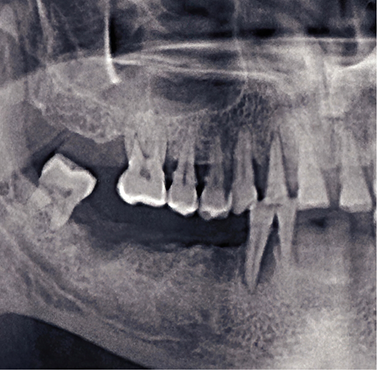

According to the American College of Prosthodontists and other resources, gum disease is the number one leading cause of tooth loss. If bacteria in your mouth penetrate and infect your connective tissues, they eventually recede from your enamel in an attempt to escape the disease. This leaves your roots exposed, and your teeth can become destabilized or dislodged altogether. However, severe tooth decay and physical trauma can also lead to missing teeth.

Once this happens, your jaw begins to thin without roots in place to stimulate new bone growth every time you bite down. This can lead to additional tooth loss and sunken cheeks, in addition to challenges in eating, speaking, or smiling confidently.